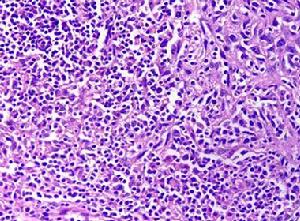

基底細胞癌起源於表面或皮膚附屬檔案的多能性基底樣細胞,可分多方向分化。癌細胞似基底細胞呈卵圓形或梭形胞核染色深,胞質少胞界不清楚。瘤實質與間質之間有對PAS染色呈陽性反應的基底帶。間質結締組織內成纖維細胞增生。間質因含大量酸性黏多糖而呈黏液樣,當標本經固定脫水後,間質內黏蛋白皺縮導致部分或全部與瘤實質分離。但通過這種現象在病理學上與鱗癌等腫瘤相區分。